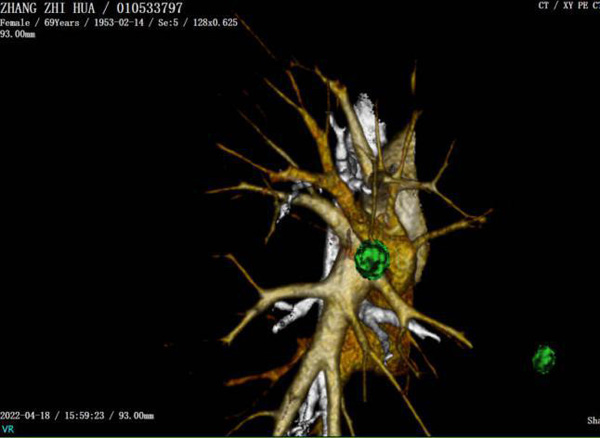

肺段切除术是肺结节及早期肺癌的重要治疗手段之一,精准的肺段手术是肿瘤学疗效和肺功能保护的前提,目标是在彻底切除病灶的同时最大程度地保留健康肺组织。胸外科团队通过专业软件对肺结节的位置进行了精确的定位,清晰显示出结节所处的肺段及靶段相关的支气管、血管情况。根据信息在术前进行详细的手术规划,确保了术中安全的、精准的切除靶肺段。

薛锋主任医师团队术中探查情况和术前的定位信息完全一致,根据术前的规划方案施行RS3+RS5切除术,术中冰冻病理提示RS3所处病灶为微浸润腺癌,RS5所处病灶为浸润性腺癌,为确保手术疗效,进一步施行RS4切除术,手术过程顺利,术中出血20毫升左右。手术切口仅有3cm,患者术后未出现相关并发症,术后48小时拔除引流管,术后1周康复出院。